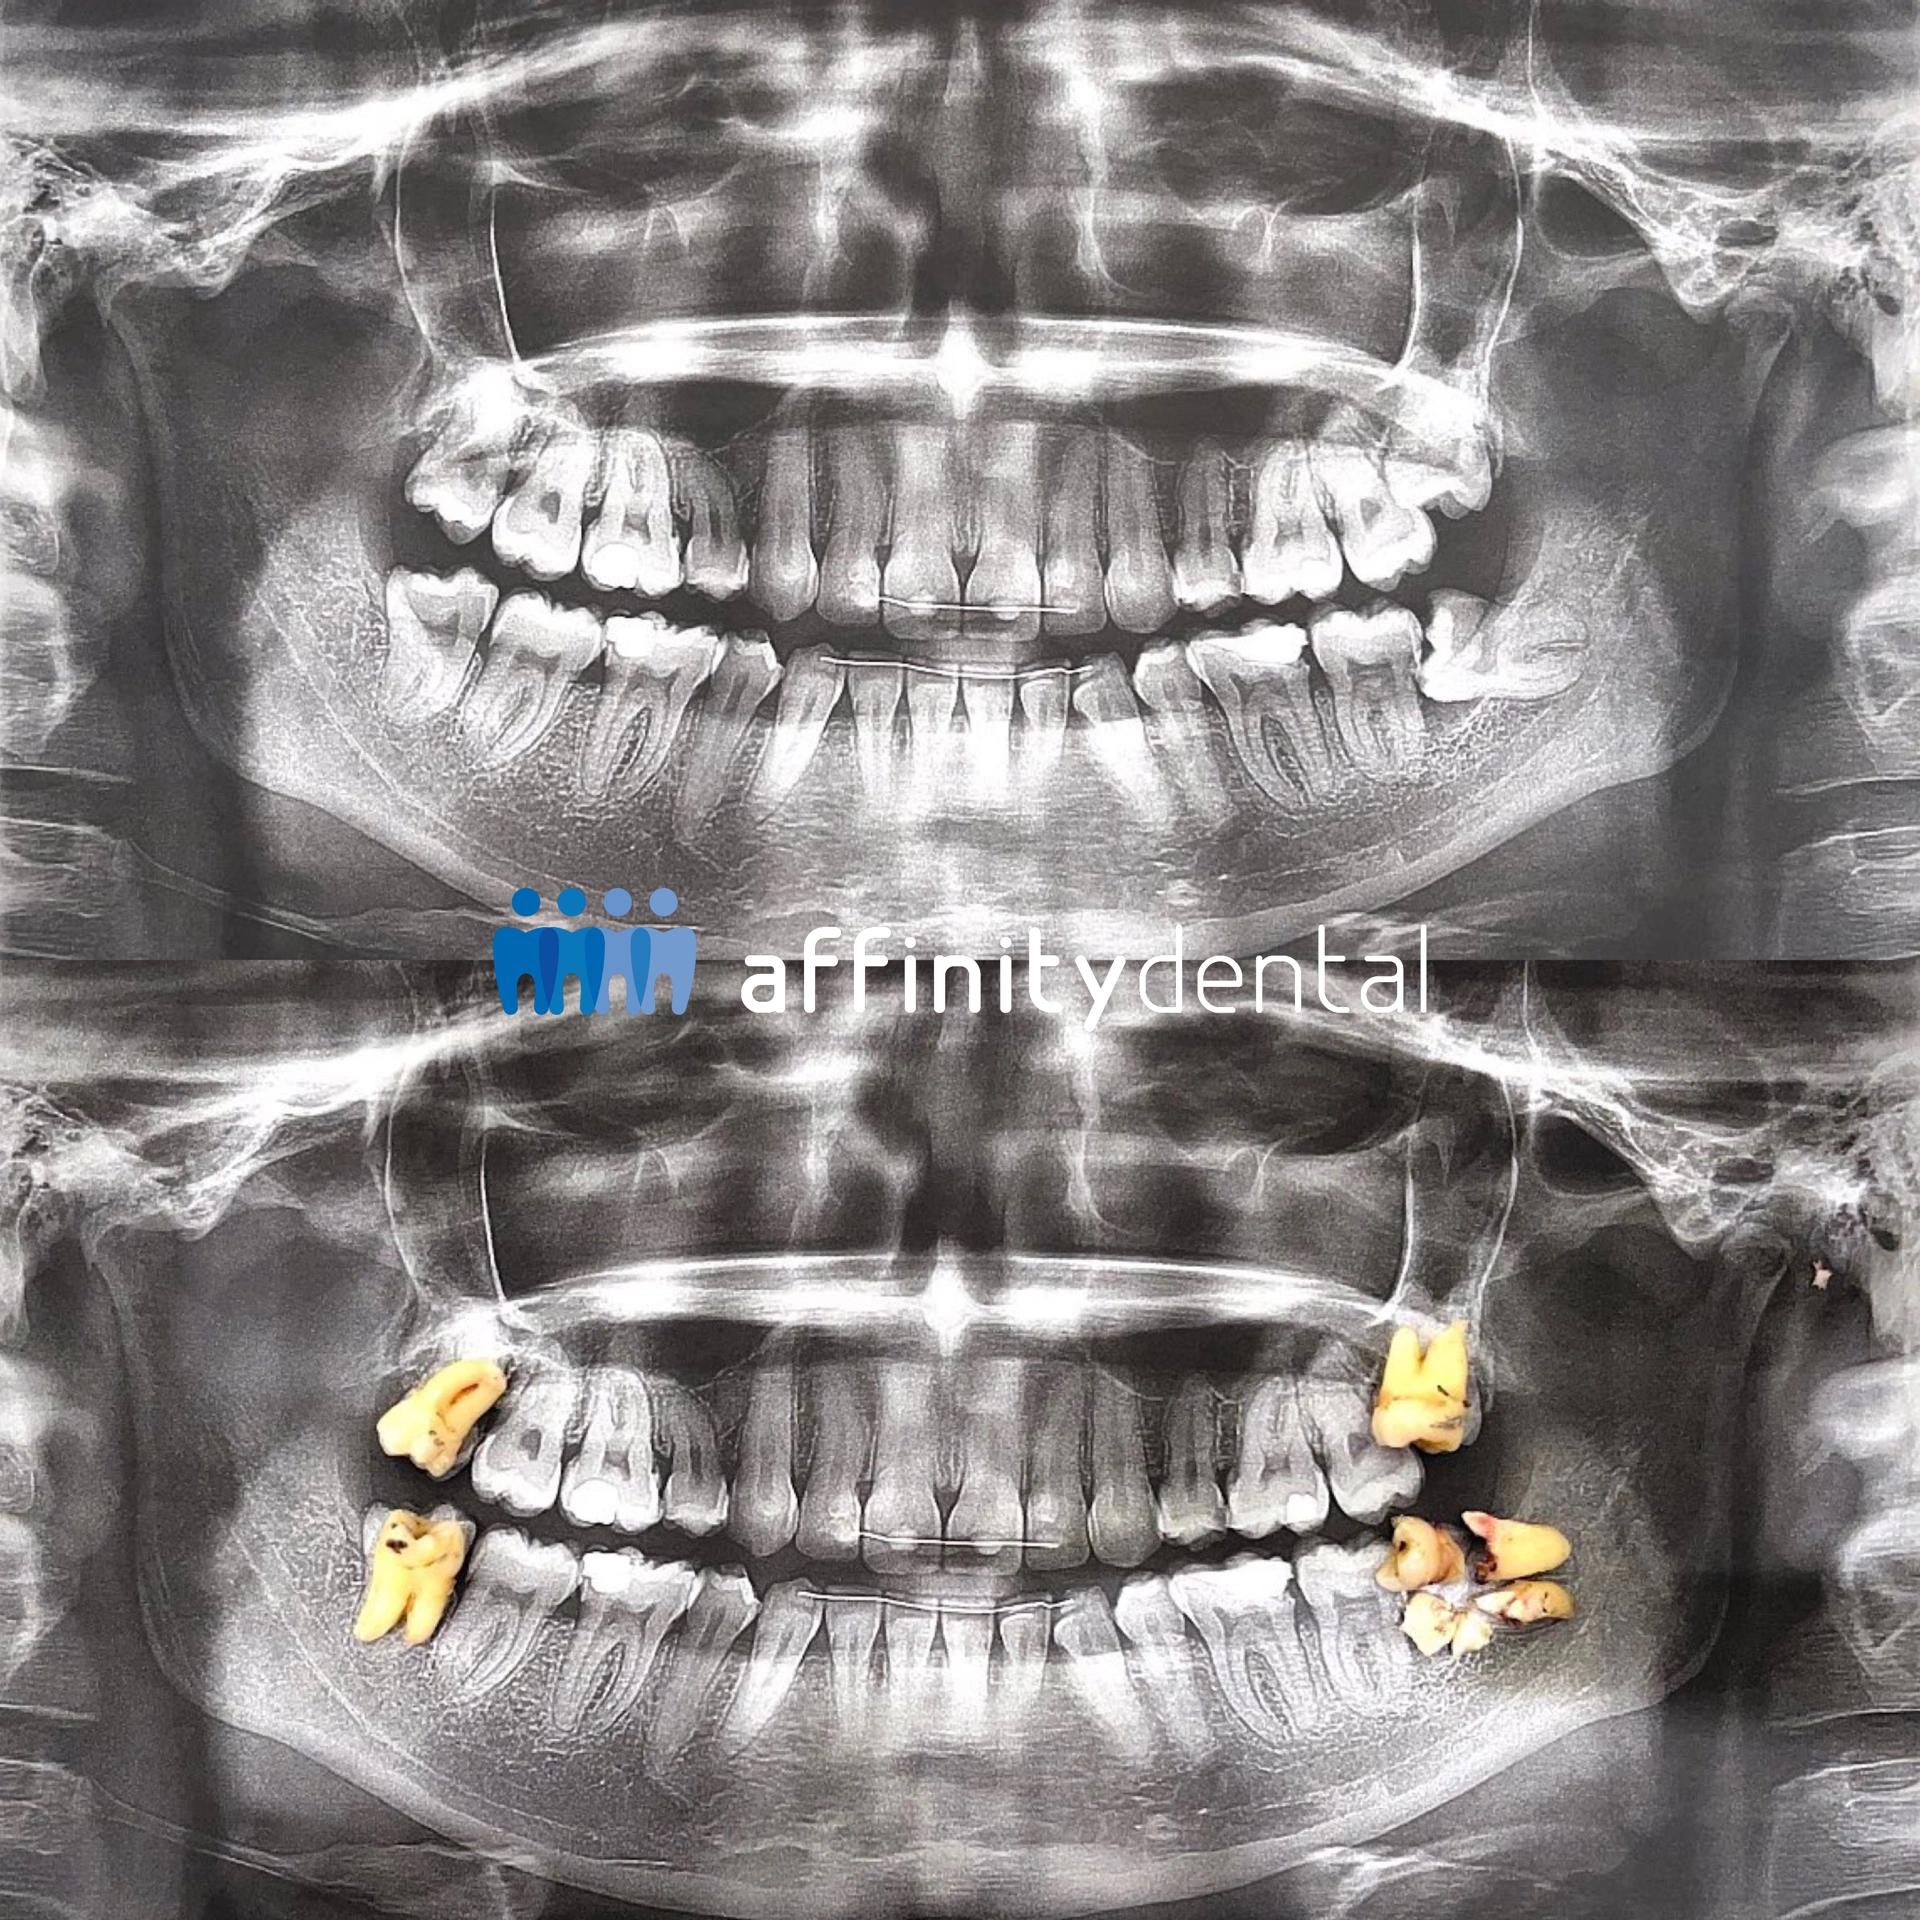

Panoramic X-ray showing before and after wisdom teeth extraction with removed teeth placed over the image at Affinity Dental Clinics BGC Stopover

Wisdom teeth extraction at Affinity Dental Clinics BGC Stopover. The X-ray compares the patient’s dentition before surgery and the removed wisdom teeth placed after extraction.